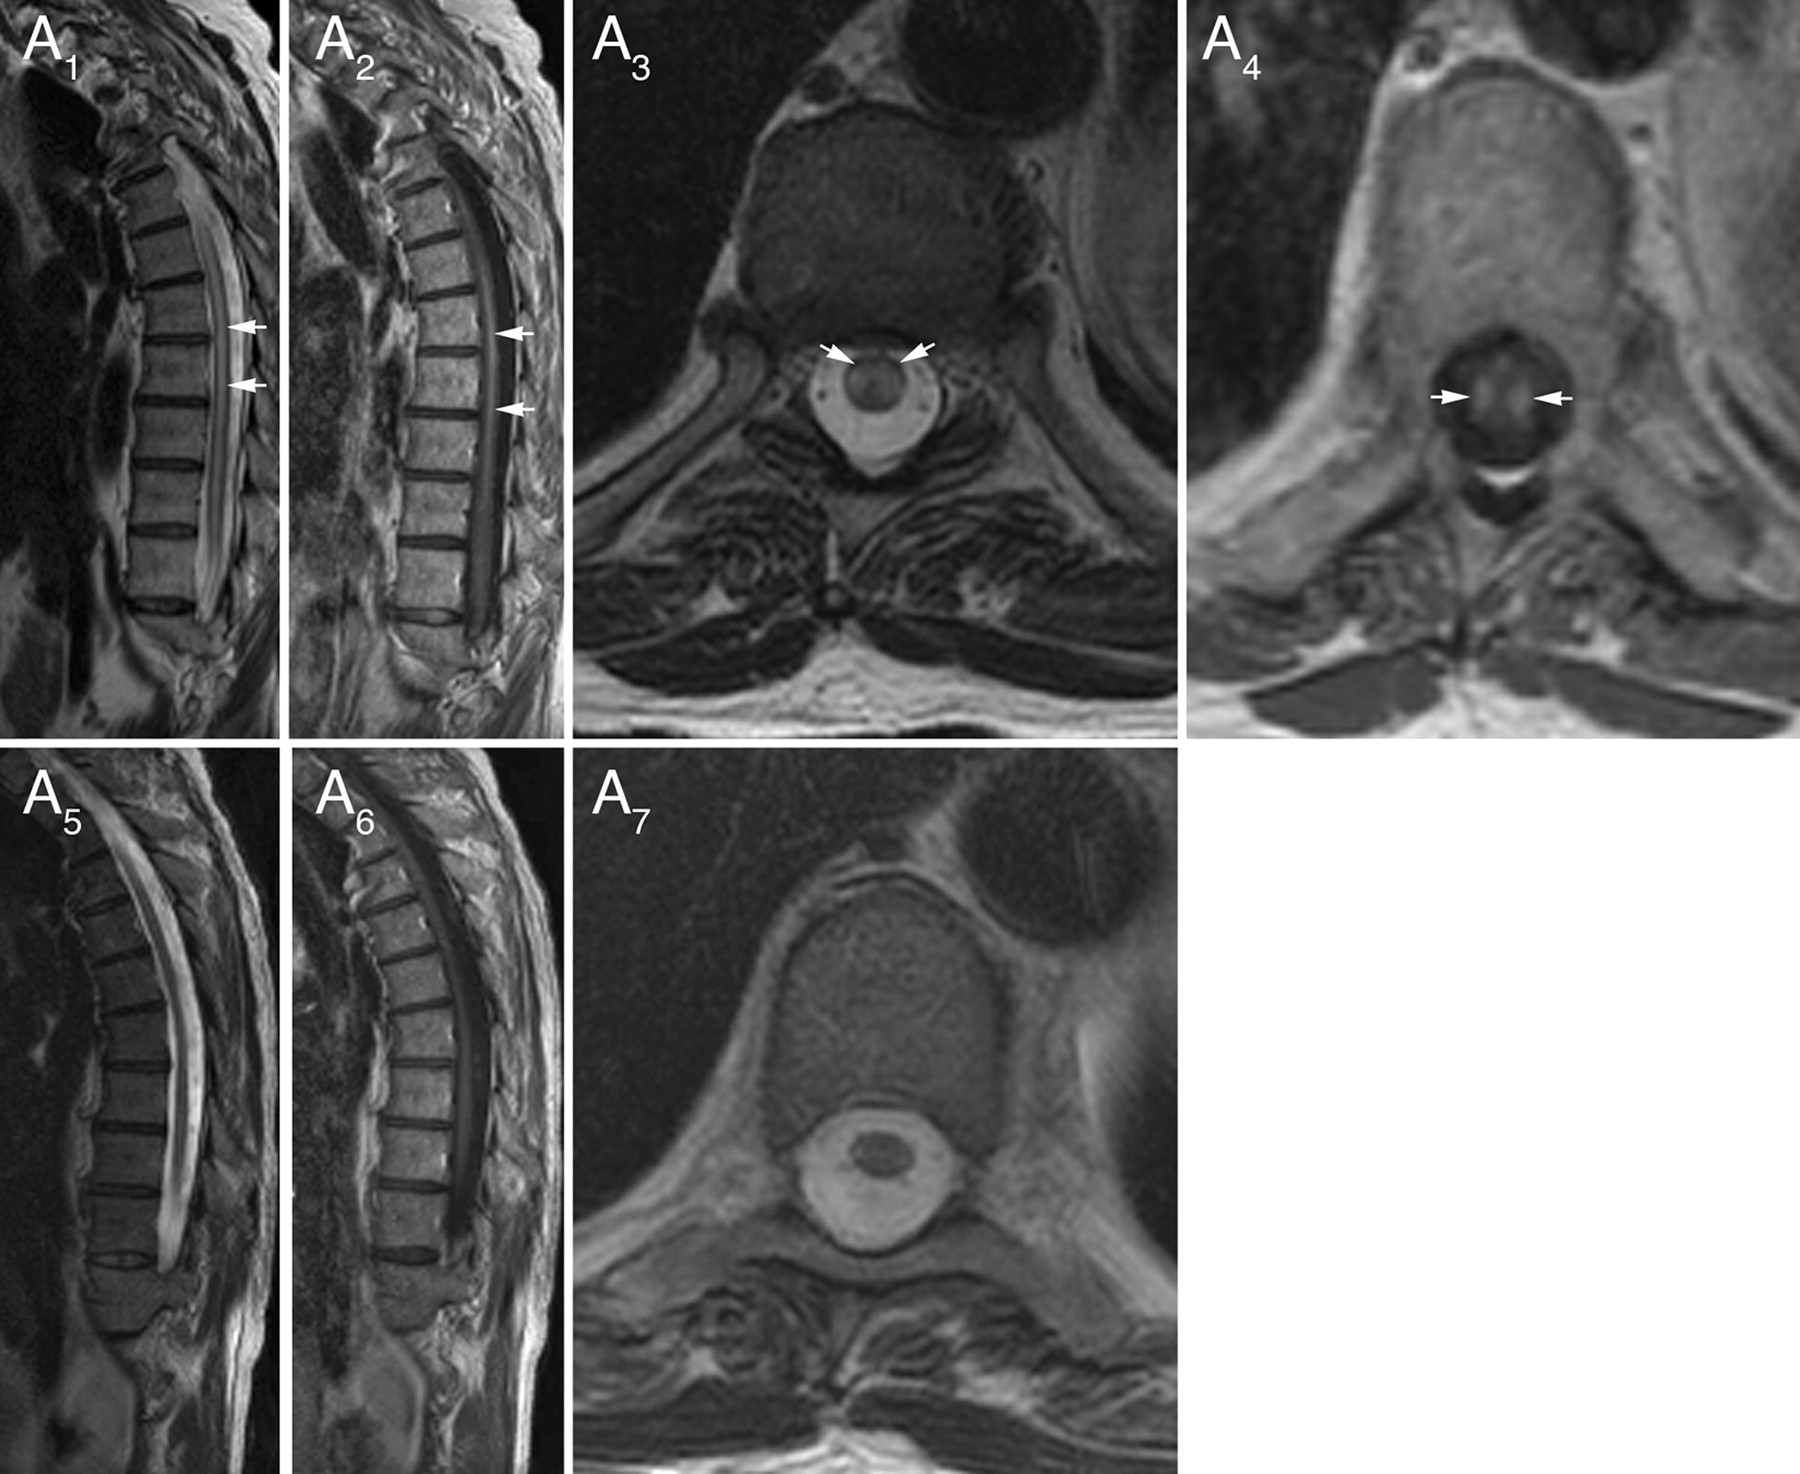

脊柱MRI(胸、颈,28日;颈,3)显示T2信号异常20例(65%)(图1和2)。14个病人纵向广泛的信号异常(> 3椎段;中位数6.5段)。15个患者对称和呼吸道或灰质在T2信号异常,在接下来的分布:侧列,5;脊柱,4;中央灰质,4;背侧柱,1;和脊柱和灰质,1。脊髓病变显示钆增强13(对称,8;不对称,5)。全身PET扫描,12例,揭示癌症3。 None had spinal cord hypermetabolic foci. MRI findings did not correlate with the cancer type or paraneoplastic autoantibody. Brain MRI performed in 26 patients showed no lesions typical of MS.

从患者MRI胸椎图片1(表)显示异常(纵向广泛T2信号1)延长超过7脊髓段与钆增强(有关2在矢状切面)。对称tract-specific T2信号异常(横向列)(轴向部分3)提高钆管理局(后4)在t1轴向图像。癌症和免疫抑制剂治疗后重复MRI演示了几乎完整的决议(5——一个7)的MRI异常;这是与临床相关的改进从依赖拐杖沃克。

尽管三分之一的患者有正常的脊柱MRI, 48%有对称的小说发现脊髓信号异常。片状钆增强报道的坏死性多种患者脊髓病,18但从我们的研究作为一个新兴的主导模式的特征多种的脊髓病是对称纵向广泛T2信号束/灰质分布异常,经常表现出对称的增强。两个类似的患者MRI发现先前文献中均有描述。1,19某些情况下表现出异常信号的模式类似于其他疾病。“猫头鹰眼”或“蛇眼”模式的T2 hyperintensity据报道在缺血性脊髓炎20.,21(预计有急性发作)。视Neuromyelitis典型纵向广泛脊髓炎,但偏爱中央灰质和钆增强而不是对称的通常是不完整的。22它还可以很少有“猫头鹰眼”或“蛇眼”外观。22所有病例在这项研究是AQP4抗体阴性。Tract-specific T2信号变化描述的维生素B12缺乏症23和肌萎缩性脊髓侧索硬化症24通常不与钆增强,临床和实验室特征排除诊断。排除了癌症转移性脊髓没有离散结节病灶实质钆增强,软膜的增强,或在PET成像hypermetabolic疫源地。25,- - - - - -,27神经通常是与leptomeningeal增强有关。28